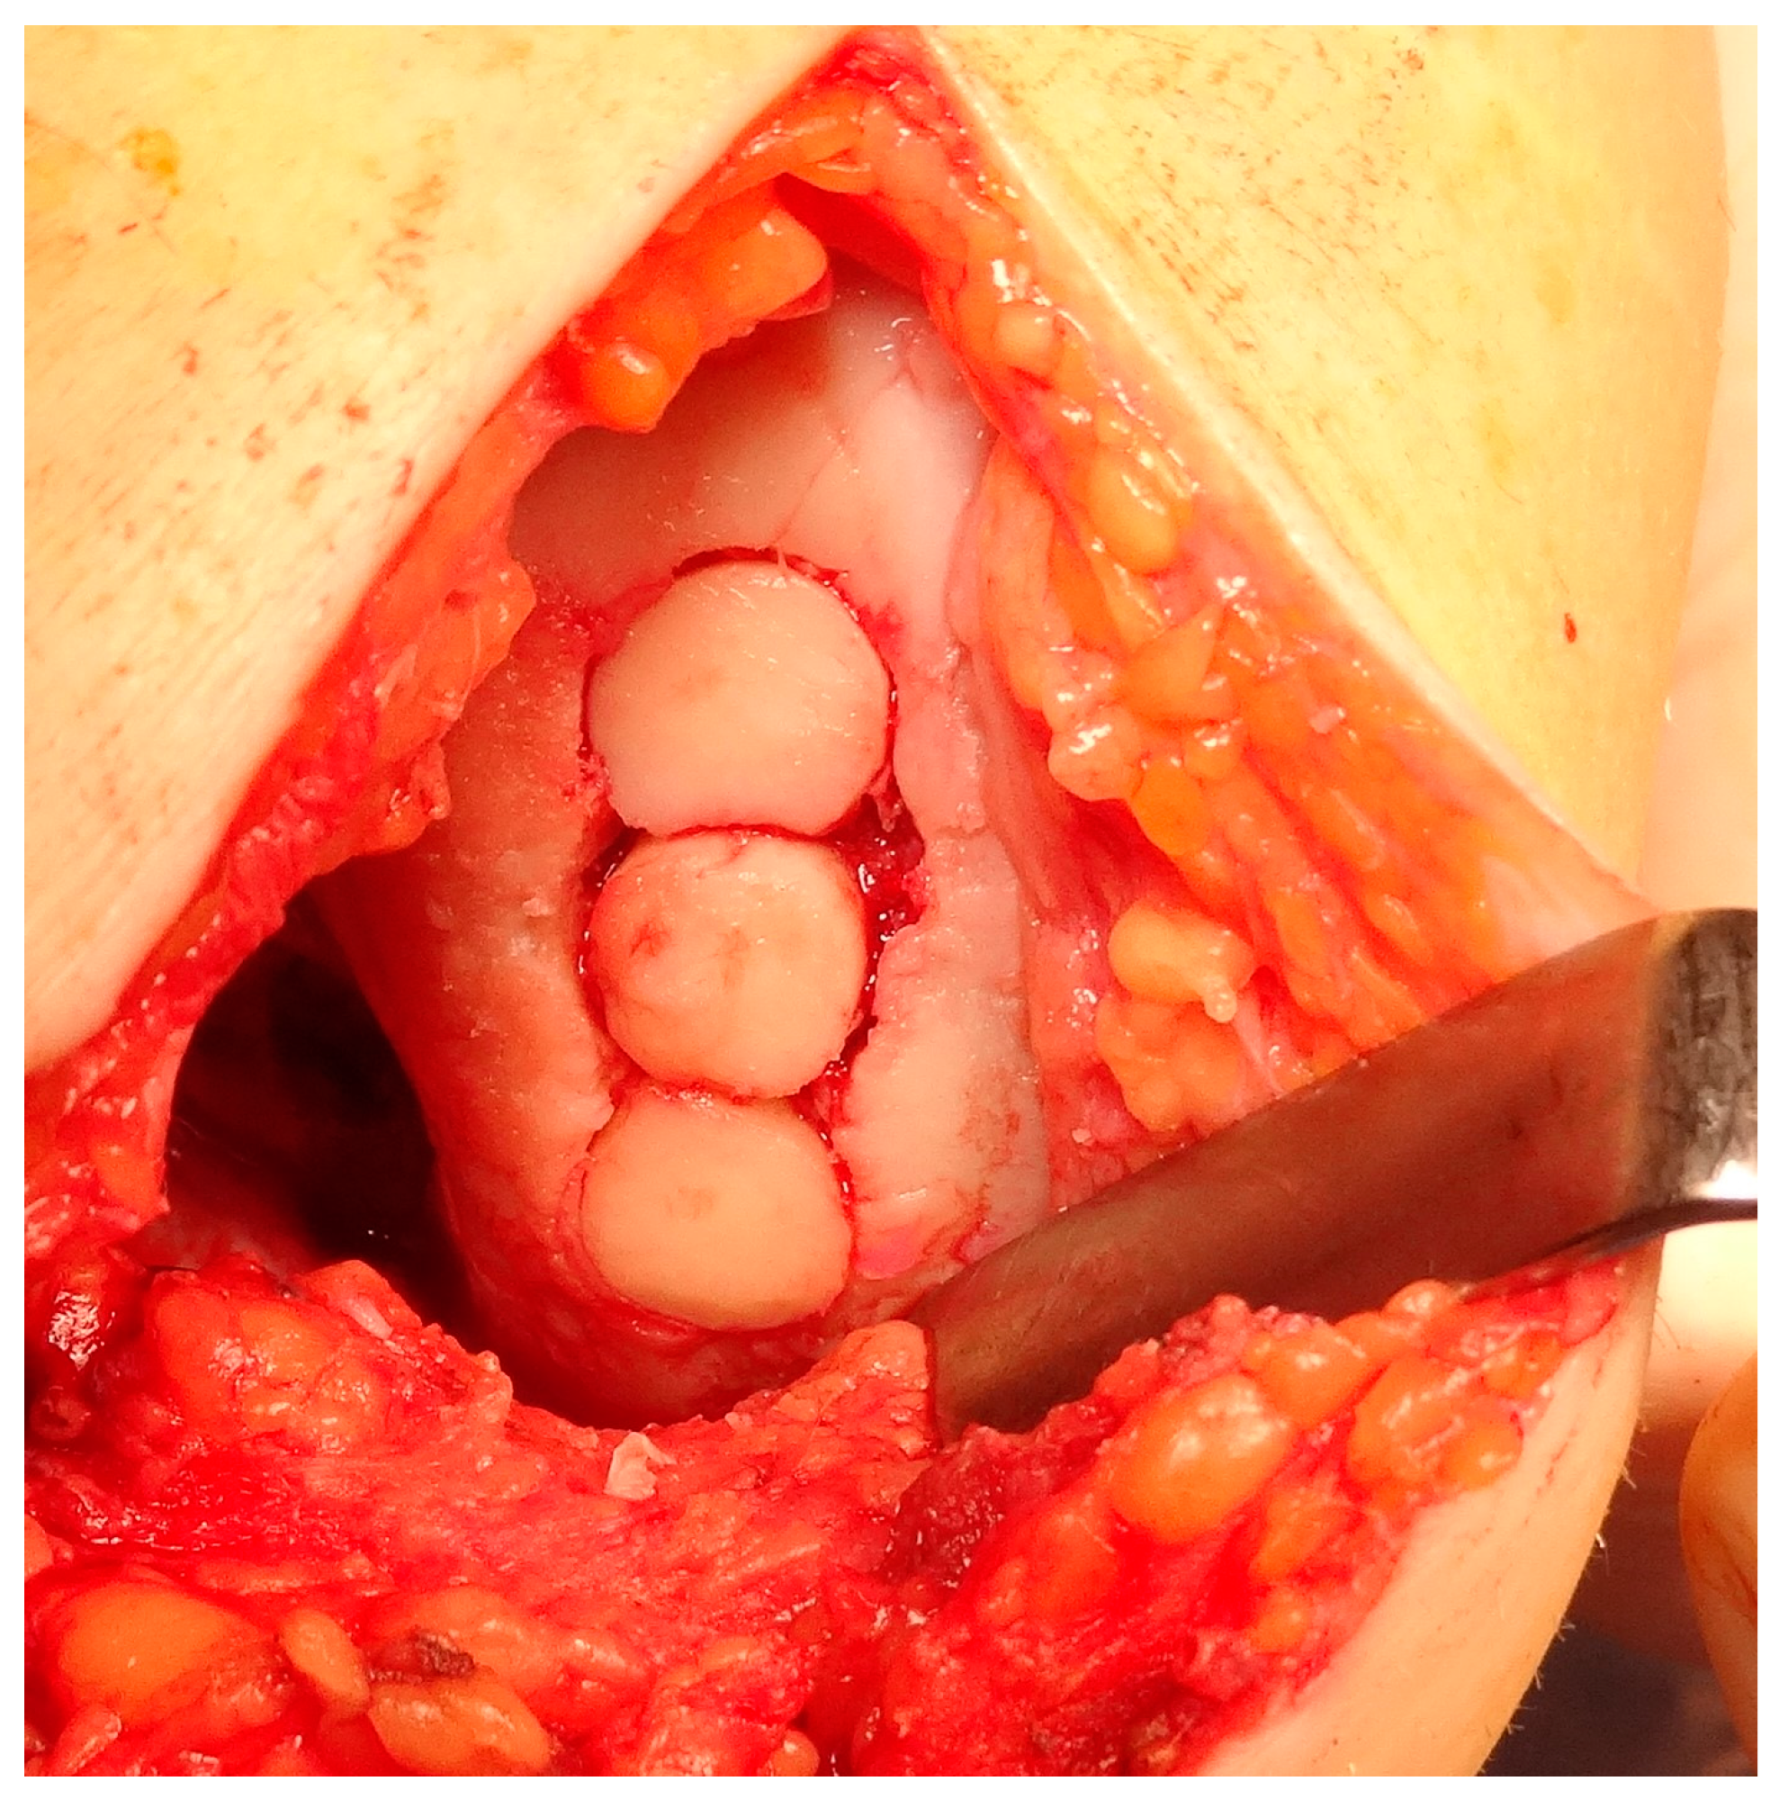

5.3. Osteochondral Autograft Transfer System (OATS)